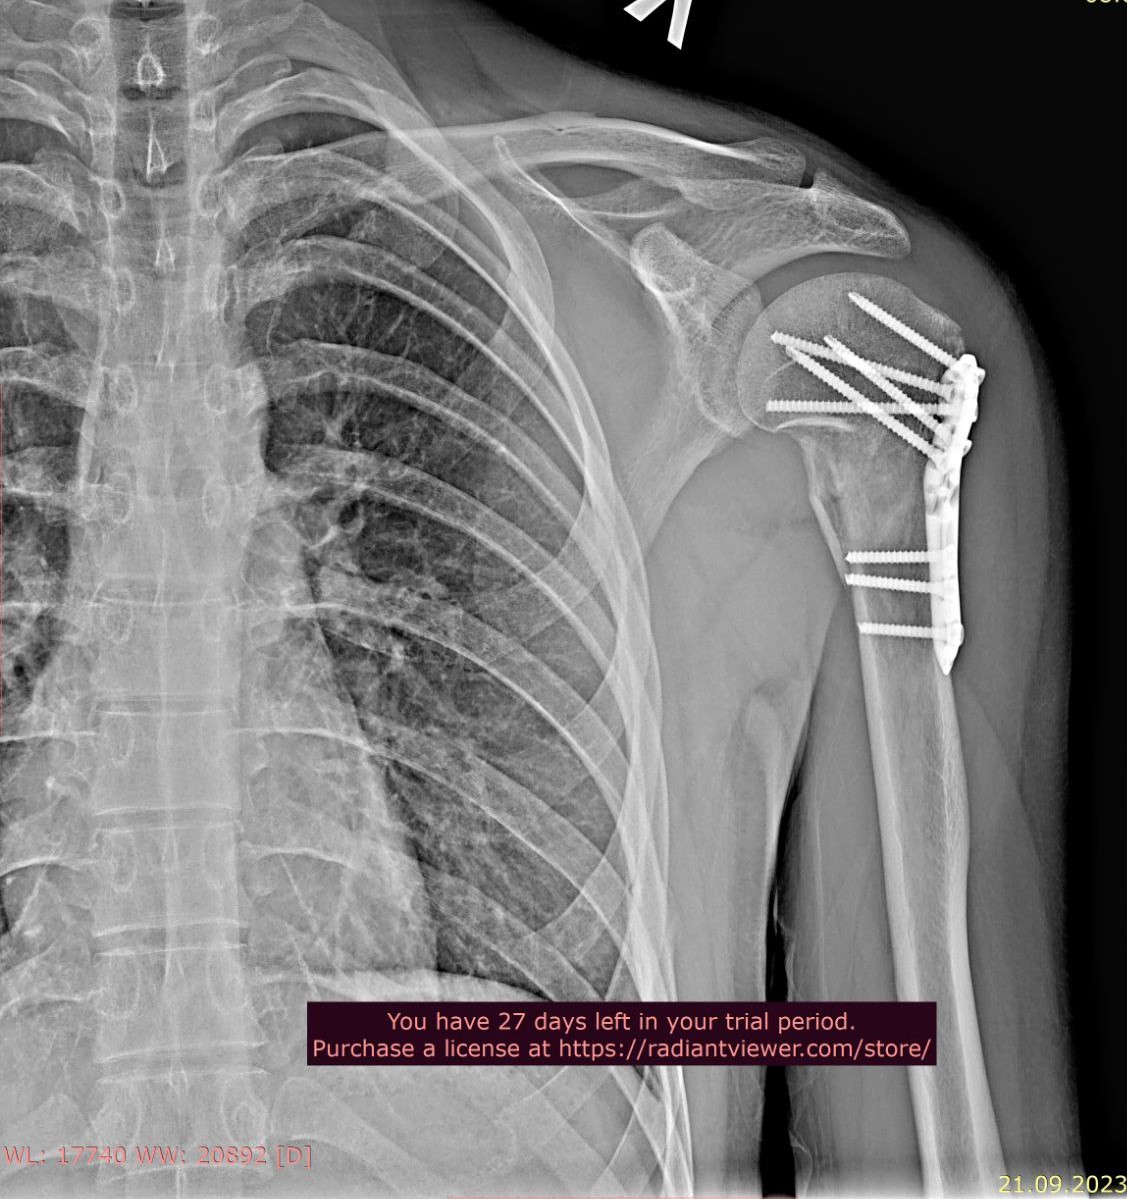

Добрый день. Два года назад упал с большой высоты, из-за чего мне установили металлоконструкции в плечевой и локтевой костях левой руки и в лучевой кости правой руки. Снимки ниже. Также имеются ограничения кисти на правой руке (из-за наличия пластины в лучевой кости), она разгибается максимум на 60 градусов из 90. Также, локтевая кость не разгибается до конца на пять градусов (что несущественно, но факт есть). Хотел бы уточнить, имею ли я возможность в моей ситуации получить категорию "В"? Спасибо.

П.jpg

Плечевая кость